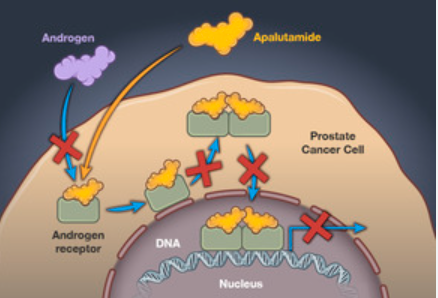

雄激素受体(AR)信号通路异常是导致mHSPC进展为mCRPC的关键,使用雄激素受体抑制剂早期干预,具有重要的临床价值。相比雄激素剥夺(ADT)治疗,传统AR抑制剂治疗患者获益有限,新一代AR抑制剂阿帕他胺三重强效抑制雄激素-雄激素受体结合能力、阻止活化雄激素受体进入细胞核以及雄激素受体与核内DNA结合。